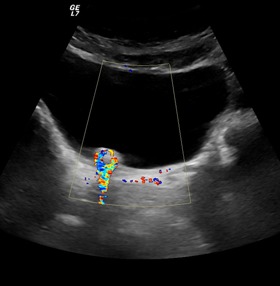

Με την έγχρωμη υπερηχοτομογραφία (Triplex) μπορούμε να ελέγχουμε την ροή του αίματος μέσα στα αγγεία του σώματος όπως η αορτή, οι καρωτίδες, οι νεφρικές αρτηρίες, οι φλέβες και αρτηρίες άνω και κάτω άκρων